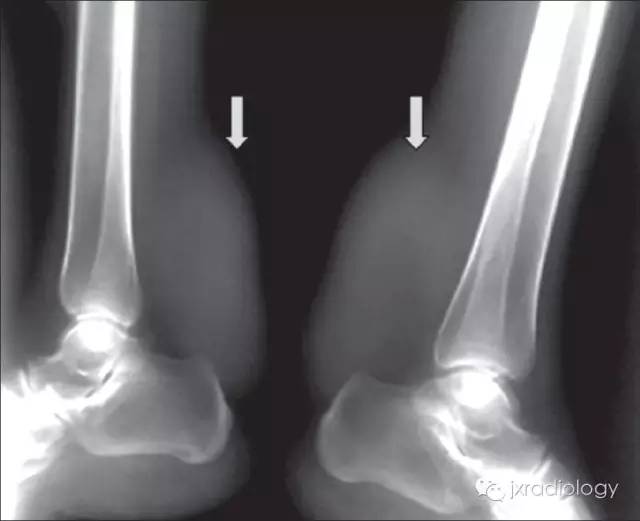

临床表现: 肌腱黄色瘤好发于跟腱、肘关节及指间关节等关节的伸肌腱部位,以跟腱最为常见。大多数情况下,其与高脂血症有关,偶可在血脂正常情况下发生。跟腱病变常为双侧性和对称性,多累及跟骨的附着处,很少引起跟腱的撕裂。

影像学表现:MRI典型病变的信号为跟腱明显梭形增粗 T1WI 像上呈顺跟腱长轴的类似肌肉的信号,表现为毛刷样改变,在 T2WI 像上也呈较低信号影,其内有斑点状短 T1 长 T2 较高信号影,T2WI 压脂像高信号区为低信号。CT:双侧跟腱部对称或单侧类梭形软组织肿块,向外膨隆,类似于肌肉密度,CT 值约 60~80Hu,与正常肌腱无法区分。